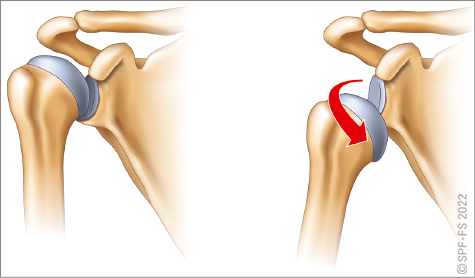

Les membres supérieurs sont chacun constitués de trois segments :

L'épaule, qui comprend, en plus de la tête de l'humérus, la scapula (anciennement omoplate) et la clavicule, est l'articulation qui relie le membre supérieur au tronc. Le coude relie le bras à l'avant-bras, et le poignet l'avant-bras à la main.

La main comporte cinq doigts, numérotés de 1 à 5 de l'extérieur vers l'intérieur et dénommés : pouce, index, majeur, annulaire et auriculaire. Chaque doigt sauf le pouce comporte trois phalanges numérotées de P1 à P3 (P2 sur le pouce), de la paume vers l'ongle. Le poing désigne la main fermée (tous les doigts pliés), et la paume désigne la face antérieure de la main sans les doigts.

Figure 2-12 : le membre supérieur